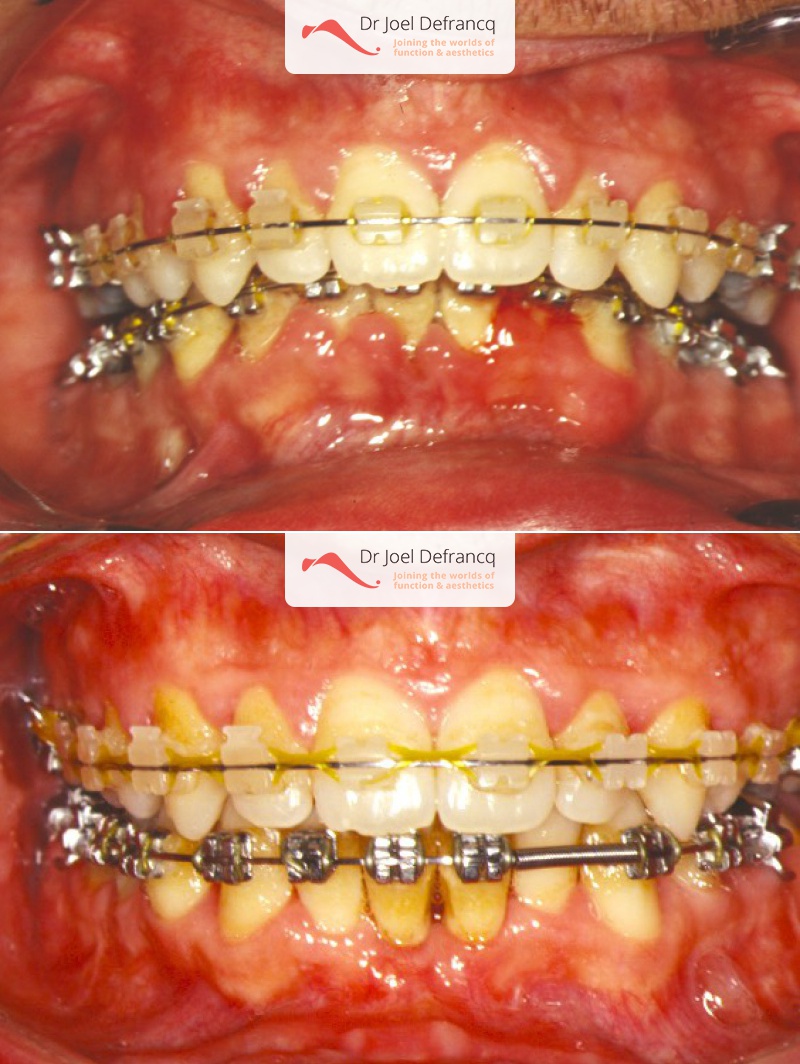

Kiro: Diepe beet, overbeet, diepe kin plooi

Dentale diagnose

- Klasse II divisie 1

Kaakchirurgie

- Verlenging onderkaak (BSSO)

- Kinchirurgie